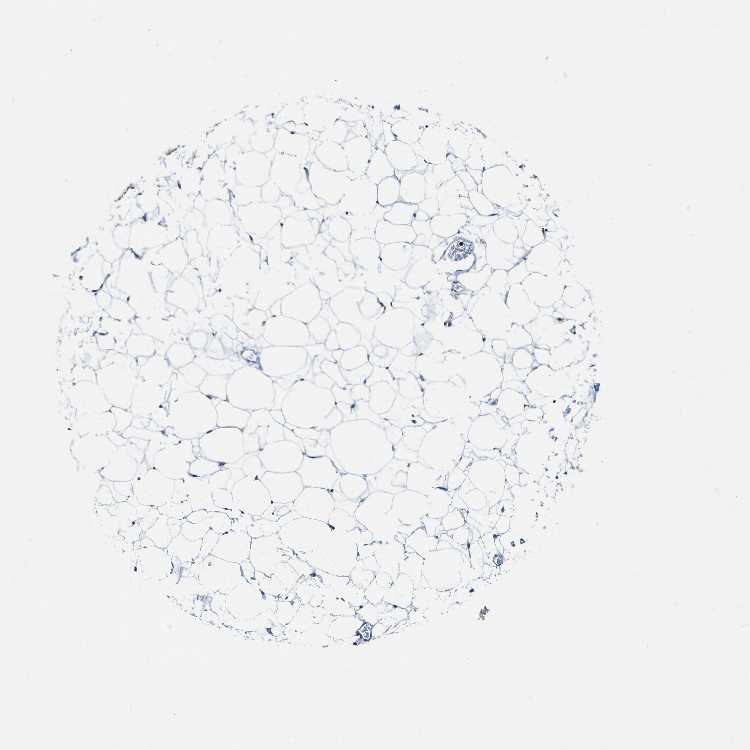

SOFT TISSUE 1 - Antibody stainingi

Antibody staining in the annotated cell types in the current human tissue is reported as not detected, low, medium, or high, based on conventional immunohistochemistry profiling in selected tissues. This score is based on the combination of the staining intensity and fraction of stained cells.

Each image is clickable and will lead to virtual microscopy that enables deeper exploration of all samples and also displays staining intensity scores, fraction scores and subcellular localization as well as patient and tissue information for each sample.

Antibody HPA017076

Fibroblasts Not detected

Peripheral nerve Not detected